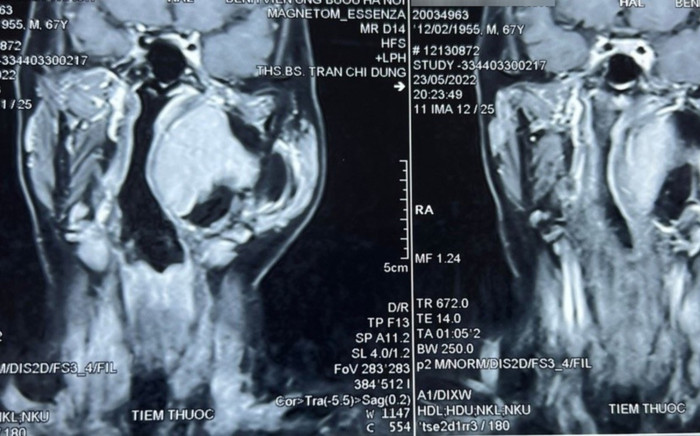

Hình ảnh chụp cộng hưởng từ khối u khoảng bên họng của bệnh nhân. (Ảnh: Bệnh viện Ung Bướu Hà Nội).

Khối u có đường kính lớn tới 10 cm nằm sâu trong khẩu kính thành họng, sát với nền sọ nên tiên lượng cuộc mổ rất khó khăn.

Khối u thuộc khoảng bên họng, trải dài từ nền sọ xuống hạ họng, đẩy lệch thành bên họng vào trong, gồm 2 phần: phần nông nằm dưới tuyến mang tai và phần còn lại nằm sâu hơn.Chẩn đoán sơ bộ ban đầu khối u là lành tính, ranh giới không rõ ràng.